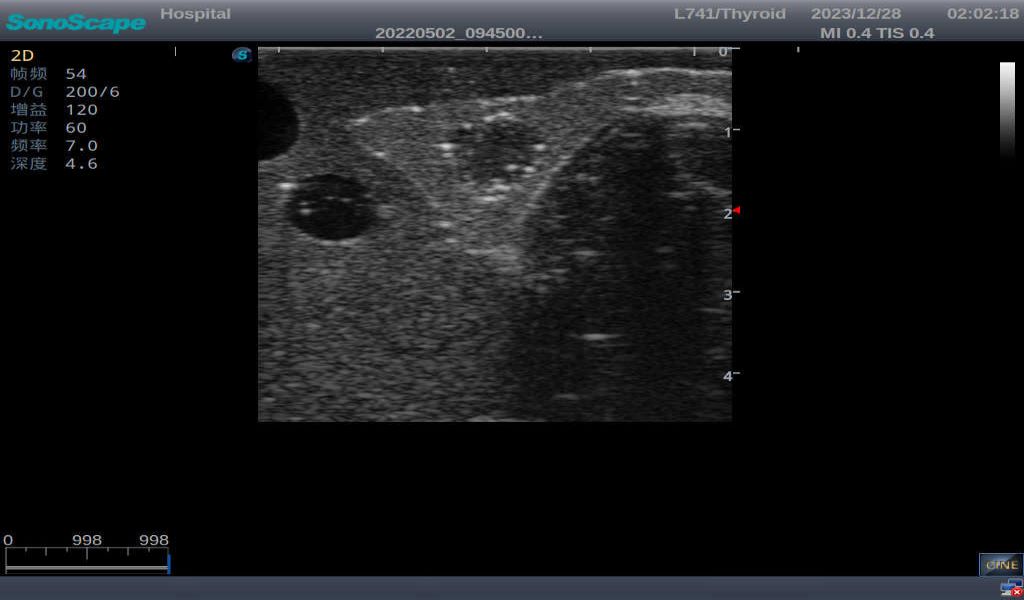

3) It comes with four (4) thyroid modules and can show five (5) ultrasonic images: normal thyroid, thyroid adenoma, thyroid cancer, nodular goiter, thyroid cyst

Thyroid cyst, which fluid area, dark and echo-free area can be seen